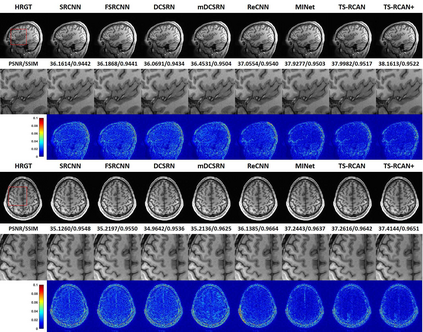

Shortening acquisition time and reducing the motion artifacts are two of the most essential concerns in magnetic resonance imaging. As a promising solution, deep learning-based high-quality MR image restoration has been investigated to generate highly-resolved and motion artifact-free MR images from lower resolution images acquired with shortened acquisition time or motion artifact-corrupted images. However, numerous problems still exist to prevent deep learning approaches from becoming practical in the clinic environment. Specifically, most of the prior works focus solely on the network but ignore the impact of various down-sampling strategies on the acquisition time. Besides, the long inference time and high GPU consumption are also the bottlenecks to deploy most of the prior works in clinics. Furthermore, prior studies employ random movement in retrospective motion artifact generation, resulting in uncontrollable severity of motion artifact. More importantly, doctors are unsure whether the generated MR images are trustworthy, making diagnosis difficult. To overcome all these problems, we adopted a unified framework of 2D deep learning neural network for both 3D MRI super-resolution and motion artifact reduction, demonstrating such a framework can achieve better performance in 3D MRI restoration tasks compared to other state-of-the-art methods and remain the GPU consumption and inference time significantly low, thus easier to deploy. We also analyzed several down-sampling strategies based on the acceleration factor, including multiple combinations of in-plane and through-plane down-sampling, and developed a controllable and quantifiable motion artifact generation method. At last, the pixel-wise uncertainty was calculated and used to estimate the accuracy of the generated image, providing additional information for a reliable diagnosis.